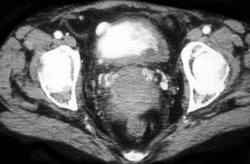

Diagnosis

Drain Near Left Kidney